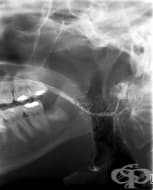

Сиалография

Сиалографията е радиографско изследване на слюнчените жлези и слюнчените канали. Най-често с този ме...